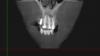

При прохождении КТ в 2011 г .была выявлена киста в области 21-21 зуба.

В 2003 году была проведена операция по резекции верхушки корней данных зубов, в 2008 году каналы зубов были заново перелечены и усилены металлическими штифтами. При наращивании коронковой части зубов 21-22 терапевт удлинил зубы вследствие чего на них увеличилась нагрузка и доставила дискомфорт.

post-23088-0-05077900-1320069184_thumb.jpg

post-23088-0-85945100-1320069186_thumb.jpg

post-23088-0-44942700-1320069187_thumb.jpg

post-23088-0-08601700-1320069188_thumb.jpg

post-23088-0-77081900-1320069268_thumb.jpg